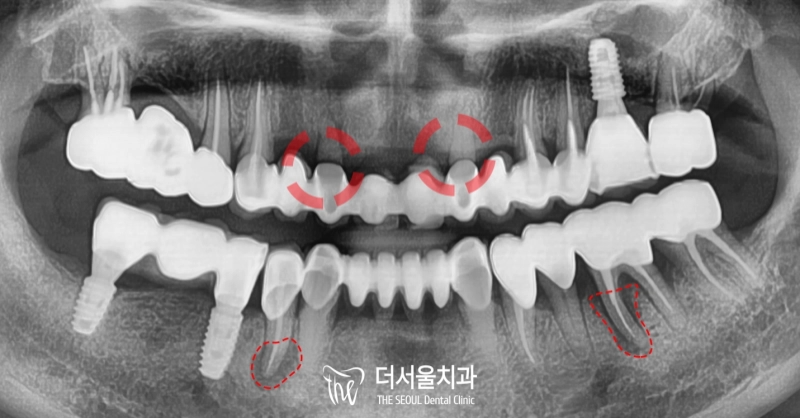

반갑습니다. 잠실 더서울 치과 박현성 원장입니다. 예전에 내원을 하셨던 환자 중에 따님분께 추천을 받아 오게 되었으며, 임플란트 수술을 받았던